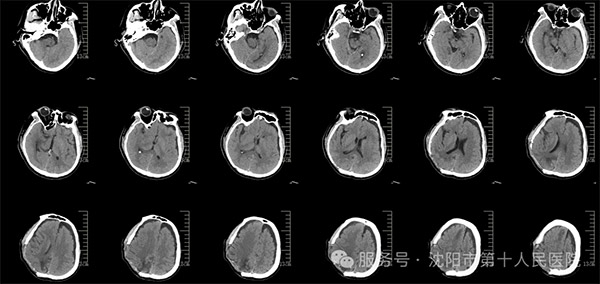

该患者在突发头晕头部摔伤,摔伤后立即被送往医院进行紧急救治。由于头部受到重创,到院时已完全昏迷,四肢瘫痪,瞳孔散大,生命垂危,急诊室予以积极的抢救,头CT检查发现患者颅内出血严重并中线移位脑疝。时间就是生命,神经中心外科景雪峰主任带领团队迅速实施开颅手术,清除了颅内的血肿,并去除了部分颅骨以降低颅内压,从而挽救了患者的生命。手术后,患者仍昏迷病情极为危重,但经过神经外科及神经重症等多学科多位专家协同会诊治疗下,患者逐步恢复自主呼吸脱离呼吸机,由重症医学科转至神经中心病房。

外伤术后影像资料